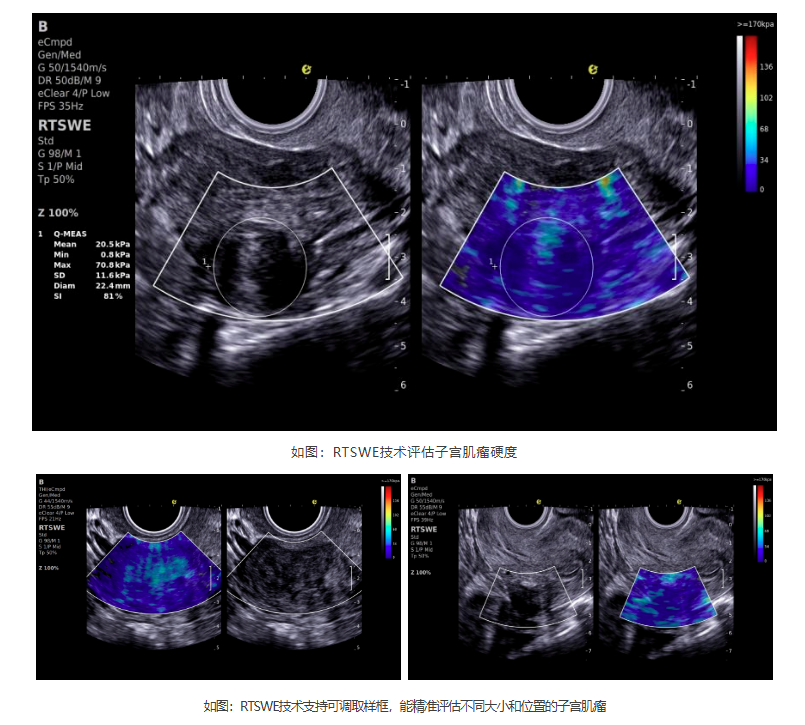

如今,利来国国际网站医疗ePascal东风系列搭载的RTSWE?实时E成像技术为肌瘤良恶性的鉴别带来了突破!该技术基于OmniSound? 平面波超快速平台,以25000帧/秒的采集帧频,实现最小0.4mm病灶的精准硬度测量。它犹如为超声检查赋予"智能触诊"能力,通过定量分析组织硬度,辅助判断肌瘤性质:

cd2301cd65513af0501835669682402.png